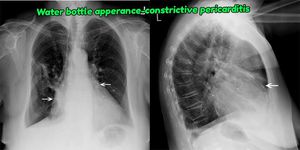

Xray finding of constrictive pericarditis